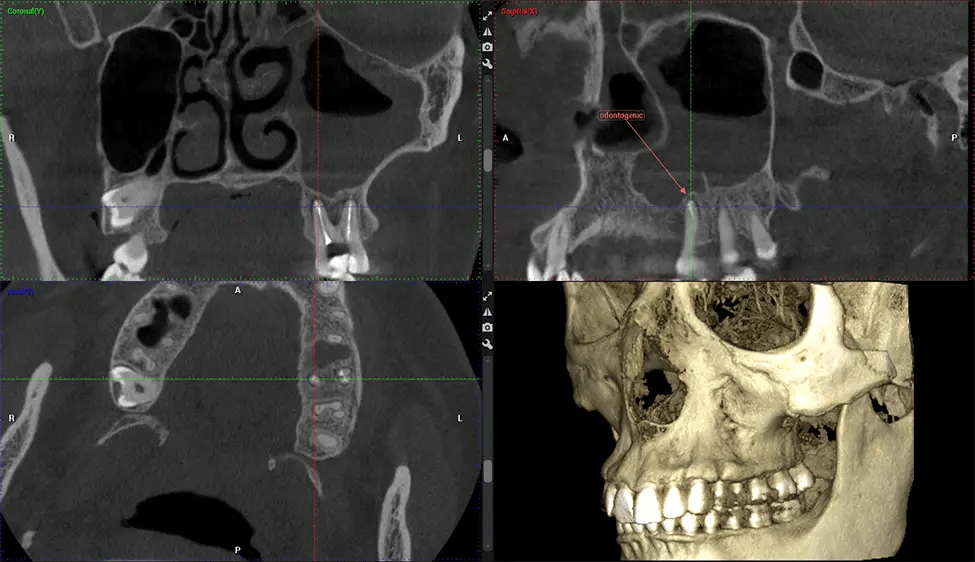

This 3D scan, called cone beam computed tomography, gives your dentist a more complete image of your oral anatomy and disease processes than a traditional X-ray. Unlike conventional X-rays, which capture a 2D image of your mouth from various angles, a 3D scan takes multiple digital X-rays for one image. It provides a complete view of your jaw, teeth, nerves, and soft tissues. This enhanced view allows dentists to detect minor issues not visible in traditional 2D scans, such as impacted wisdom teeth or bone fractures in the sinus cavity.

There are many benefits to using CBCT technology, especially compared to the traditional 2D X-ray format. One of the most significant advantages of CBCT scans is that they provide much more information than traditional X-rays. A scan lets your dentist see images from all angles of your jaw and mouth, including your sinuses, nasal cavity, cheekbones, and other surrounding areas. This added information helps your dentist craft a comprehensive treatment plan that addresses all aspects of your oral health.

After the scanning process, the captured X-ray images are processed by the CBCT software, which applies algorithms to reconstruct a detailed 3D image of the scanned area. The software compiles these individual X-ray images and creates a digital 3D representation of the patient’s anatomy. The reconstructed 3D CBCT image can be viewed and analyzed by the dentist or radiologist. This image can be manipulated, rotated, and zoomed in or out to examine specific structures and evaluate the patient’s condition.